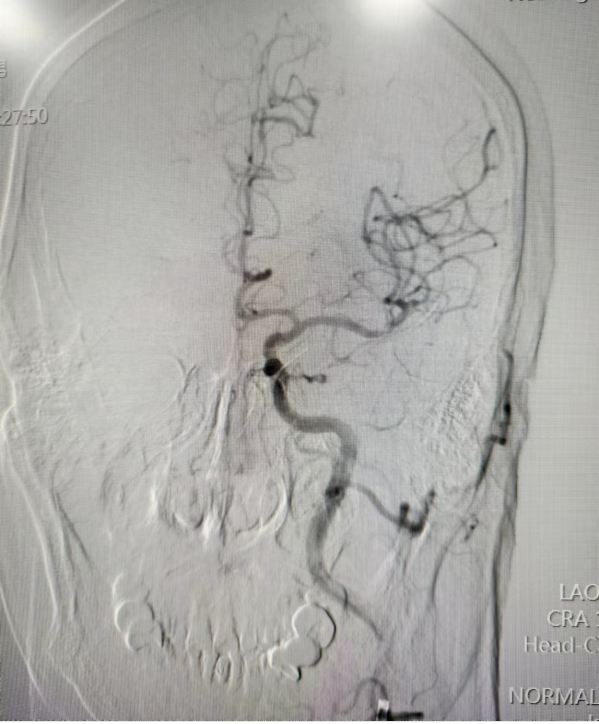

术后开通影像

术中予左侧大脑中动脉Solitaire支架取栓+中间导管负压抽吸成功取出血栓,恢复血管再通。